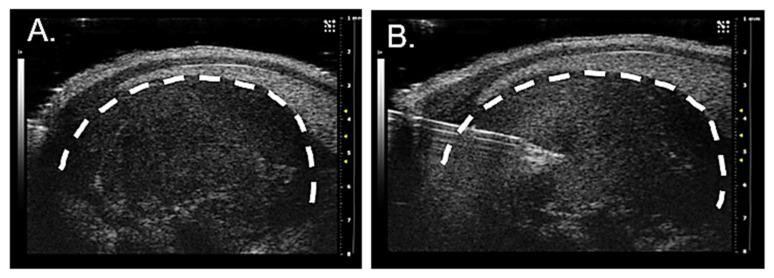

Dense tumor innervation is associated with enhanced cancer progression and poor prognosis. We observed innervation in breast, prostate, pancreatic, lung, liver, ovarian, and colon cancers. Defining innervation in high-grade serous ovarian carcinoma (HGSOC) was a focus since sensory innervation was observed whereas the normal tissue contains predominantly sympathetic input. The origin, specific nerve type, and the mechanisms promoting innervation and driving nerve-cancer cell communications in ovarian cancer remain largely unknown. The technique of neuro-tracing enhances the study of tumor innervation by offering a means for identification and mapping of nerve sources that may directly and indirectly affect the tumor microenvironment. Here, we establish a murine model of HGSOC and utilize image-guided microinjections of retrograde neuro-tracer to label tumor-infiltrating peripheral neurons, mapping their source and circuitry. We show that regional sensory neurons innervate HGSOC tumors. Interestingly, the axons within the tumor trace back to local dorsal root ganglia as well as jugular-nodose ganglia. Further manipulations of these tumor projecting neurons may define the neuronal contributions in tumor growth, invasion, metastasis, and responses to therapeutics.

密集的肿瘤神经支配与癌症的进展和预后不良有关。我们观察到乳腺癌、前列腺癌、胰腺癌、肺癌、肝癌、卵巢癌和结肠癌存在神经支配。由于观察到感觉神经支配,而正常组织主要含有交感神经输入,因此高等级浆液性卵巢癌(HGSOC)中的神经支配的定义是一个重点。神经支配的起源、特定神经类型以及促进神经-癌细胞通讯的机制在卵巢癌中仍然很大程度上未知。神经追踪技术通过提供一种识别和绘制可能直接和间接影响肿瘤微环境的神经来源的方法,增强了对肿瘤神经支配的研究。在这里,我们建立了 HGSOC 的小鼠模型,并利用图像引导的逆行神经示踪剂微注射来标记肿瘤浸润的周围神经元,绘制其来源和回路。我们表明,局部感觉神经元支配 HGSOC 肿瘤。有趣的是,肿瘤内的轴突回溯到局部背根神经节和颈静脉神经节。对这些肿瘤投射神经元的进一步操作可能会确定神经元在肿瘤生长、侵袭、转移和对治疗的反应中的贡献。